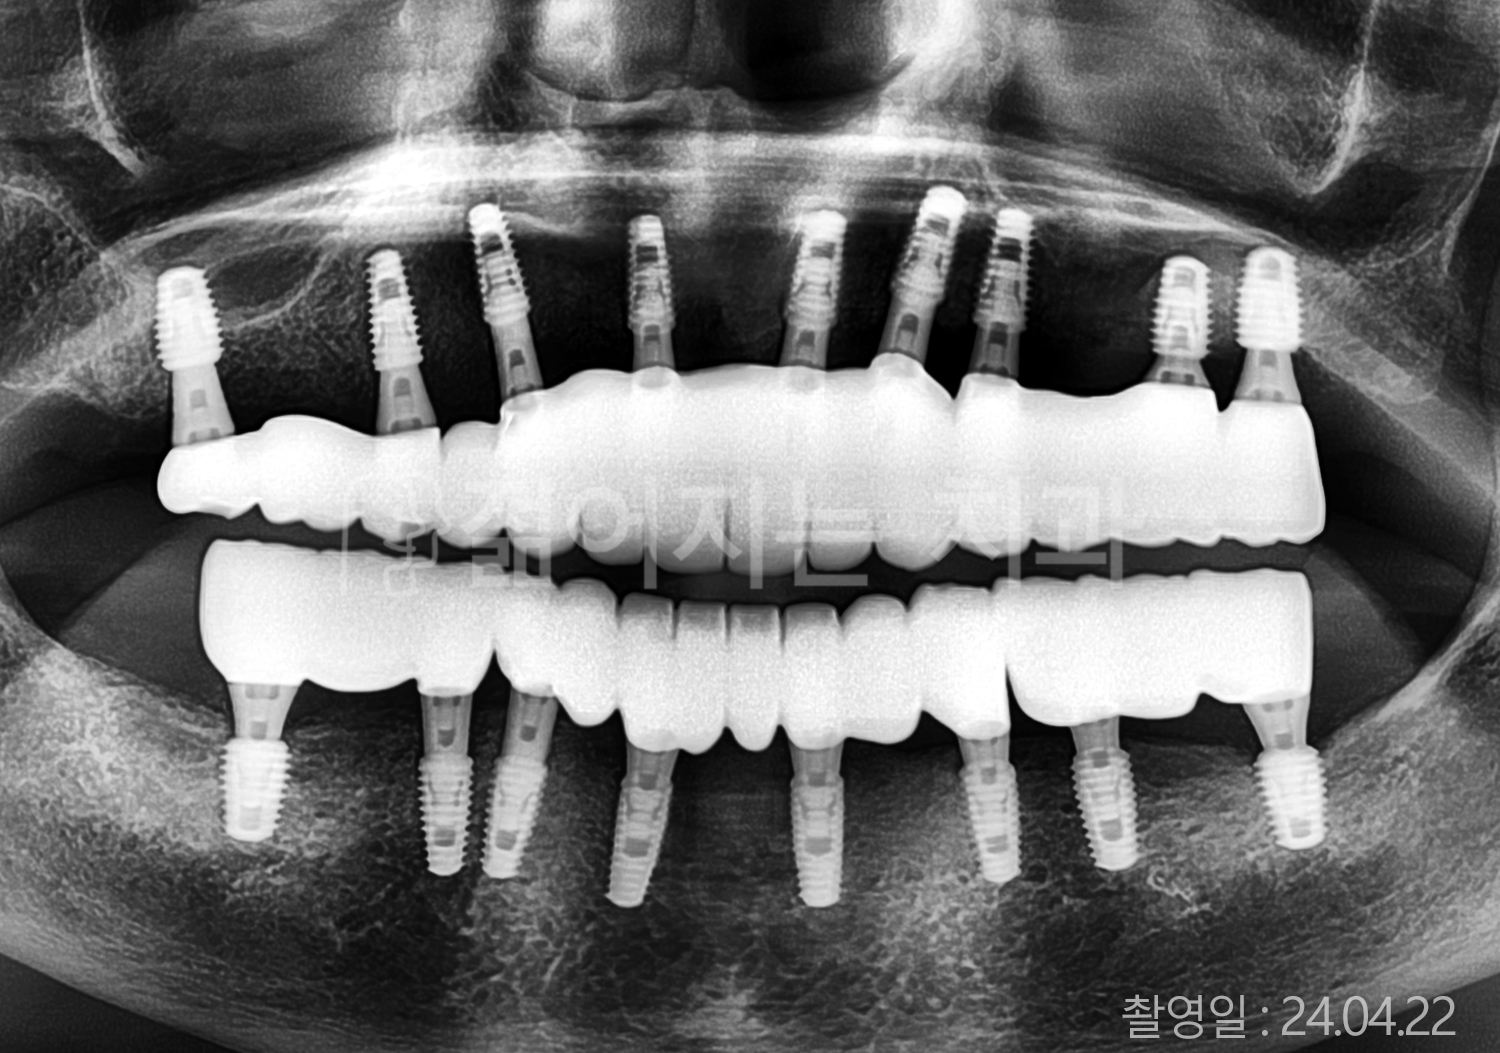

• 80대 전체치아 10개 이상 임플란트

• 60대 고혈압, 당뇨, 고지혈증 전체치아 10개 이상 임플란트

• 60대 전체치아 10개 이상 임플란트

• 60대 고혈압, 고지혈증 전체치아 10개 이상 임플란트

• 50대 고혈압, 당뇨, 고지혈증 전체치아 10개 이상 임플란트

• 70대 골다골증, 파킨스병 전체치아 10개 이상 임플란트

• 40대 전체치아 10개 이상 임플란트

• 60대 골다골증 전체치아 10개 이상 임플란트

• 40대 고혈압 전체치아 10개 이상 임플란트

• 50대 전체치아 10개 이상 임플란트

• 70대 전체치아 10개 이상 임플란트